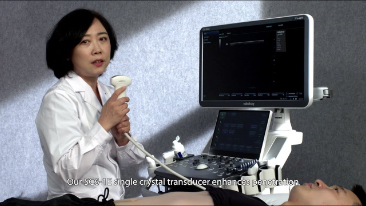

Avec sa connaissance approfondie des besoins cliniques, l'objectif de Mindray est de vous proposer des solutions d'imagerie complètes, pour des diagnostics plus prÊcis et un traitement mieux ciblÊ dans diffÊrentes spÊcialitÊs.